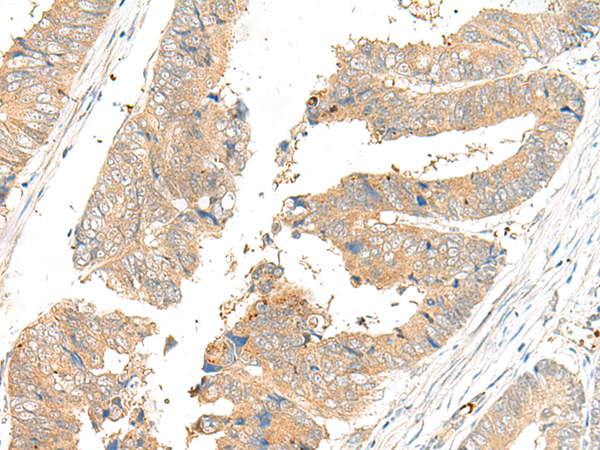

IHC positive control: |

Human colorectal cancer |

IHC Recommend dilution: |

40-200 |